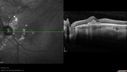

SPECTRALIS-SD-OCT SCAN: The OCT scan in the right eye shows the macula to be dry. The left eye shows macular edema. The photos confirm the retinal hemorrhage in the left eye.

Punctate Inner Choroidopathy - Recurrent CNVM 4 years after initial treatment Left Eye - SD OCT762 viewsJune 7, 2012. This pleasant 35-year-old woman noticed decreasing vision in the left eye recently. She returns now noticing the vision in the left eye is declining. OD 20/50, OS 20/80. OS: Vertical C/D ratio is 0.3. There is a scar just inferonasal to the fovea, which has grown some towards the fovea with a little blood just under the fovea.

(0 votes)